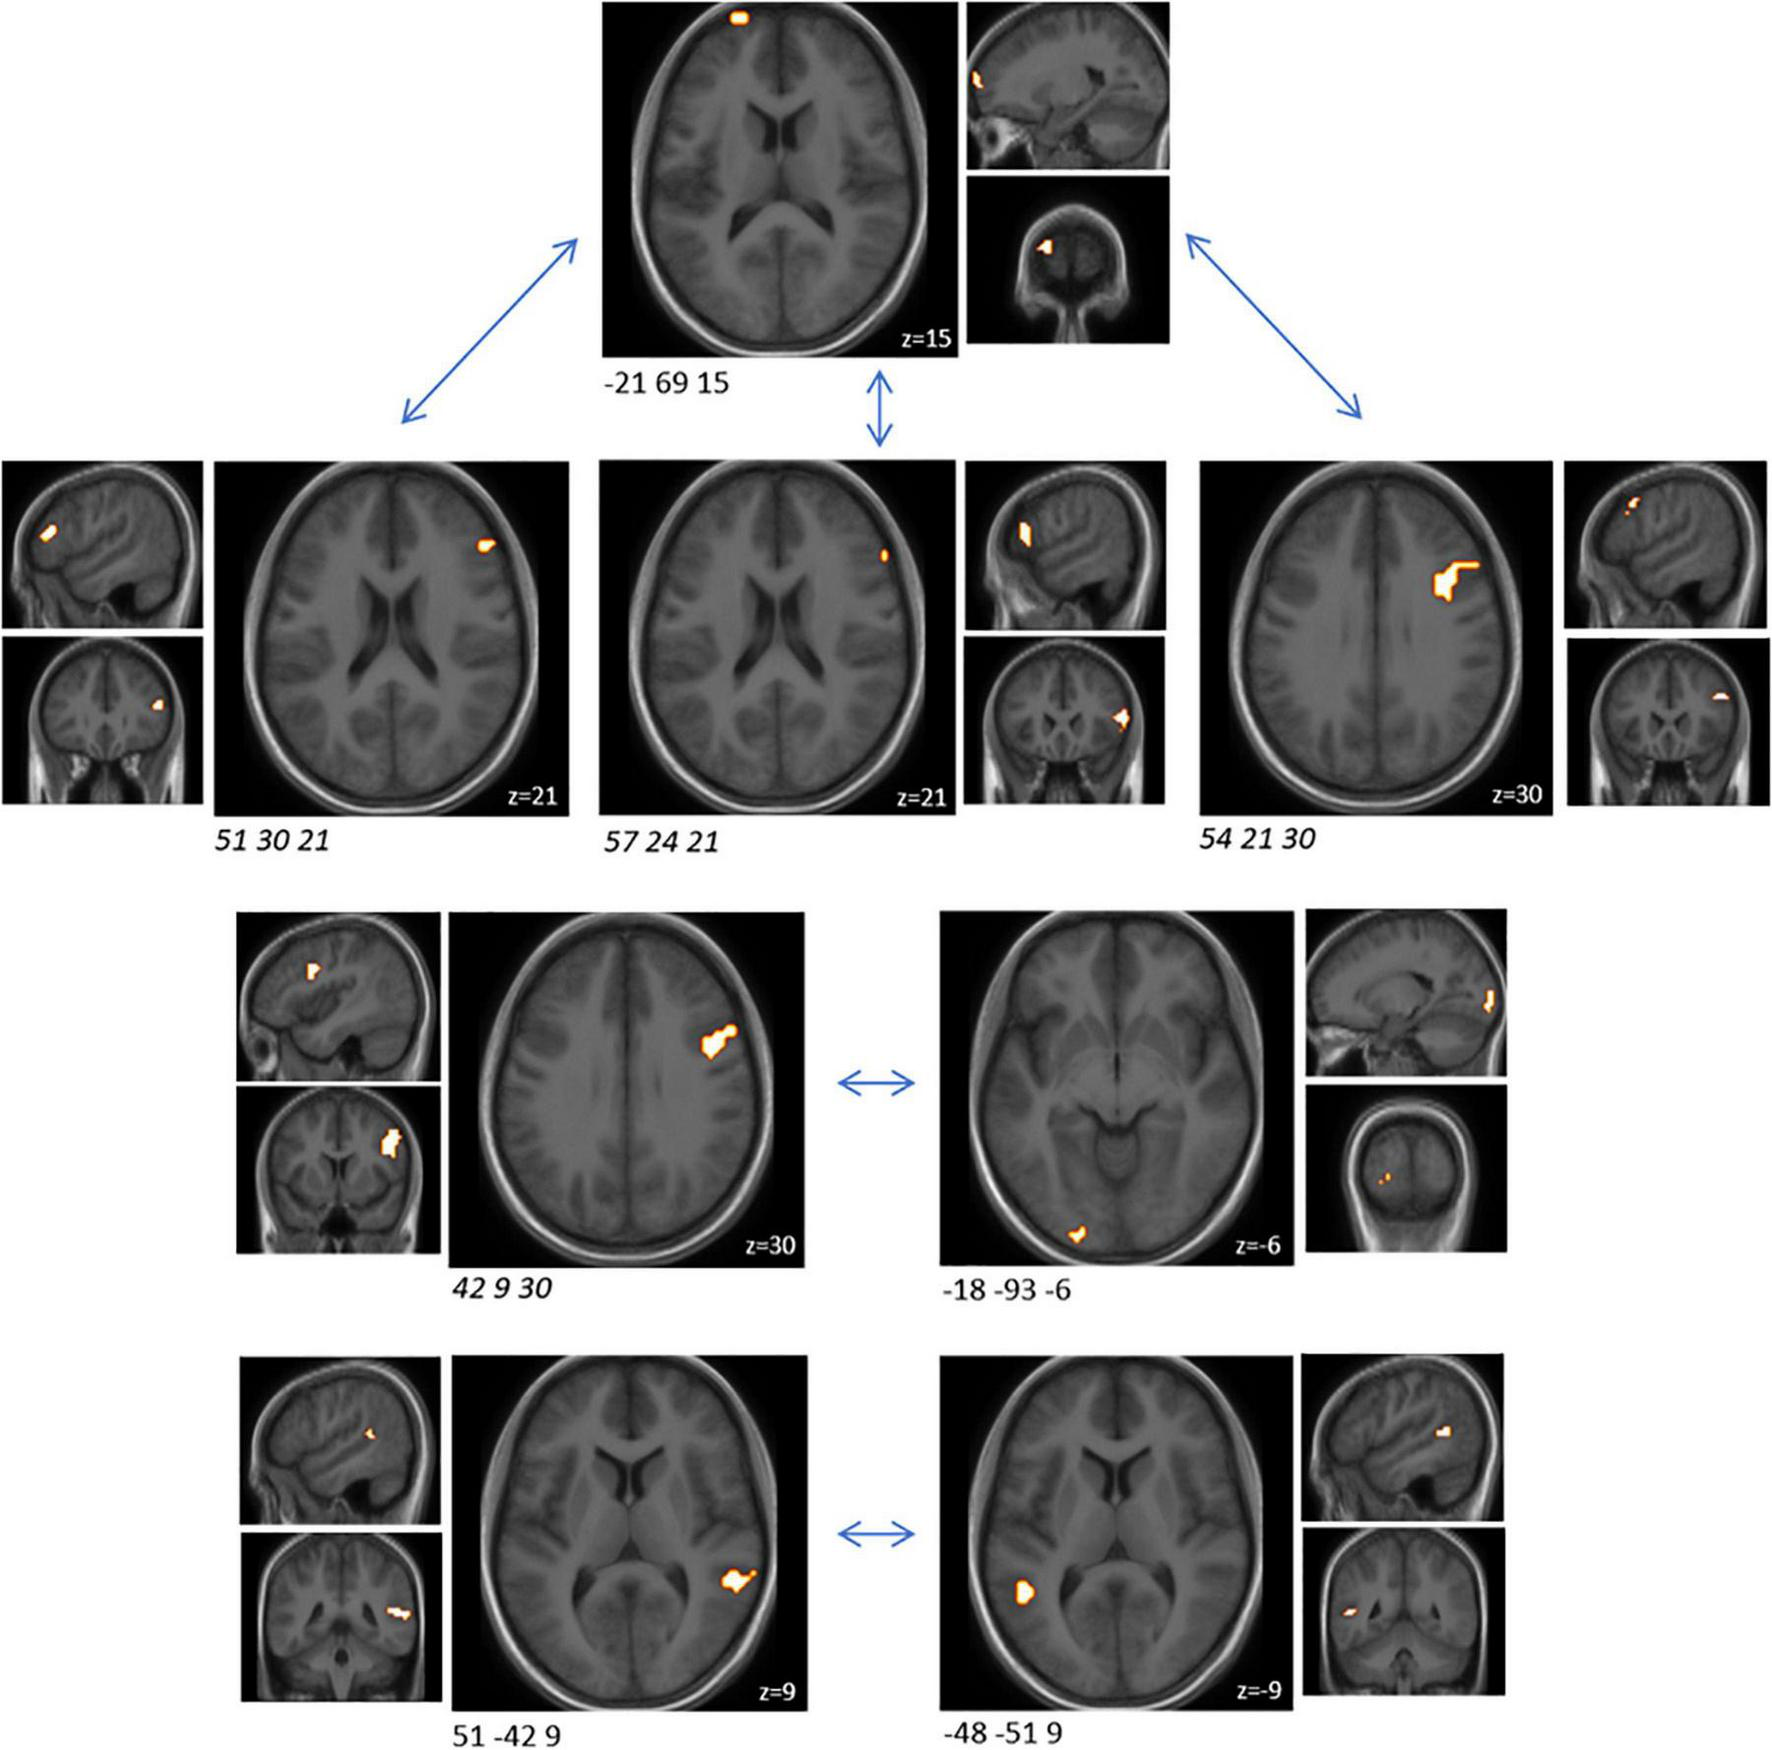

A cluster-based analysis was performed in order to focus on functionally altered sets of voxels. Significant (p < 0.05) activation (without correction for multiplicity) was observed in three predefined sub-clusters when comparing the interventions with respect to the differential activity evoked by the challenge paradigm. Two of these sub-clusters were located within the predefined ROIs, both within the orbitofrontal cortex (Table 2 and Figure 2). All clusters showed an increased activation upon probiotic intervention compared to placebo.

Figure 2. Sub-clusters that were found to be associated with significant (p < 0.05) changes in brain activity between both interventions (probiotic > placebo) before multiplicity correction, during the EAT paradigm. Two of these sub-clusters covered predefined ROIs (italic). Clusters are superimposed on average anatomical scans. Clusters can be identified by the coordinates of their peak (x y z). EAT, emotional attention task; ROI, region of interest.

In order to understand how the probiotic intervention altered task-related functional connectivity, a connectivity analysis between all sub-clusters that showed altered brain activity when comparing the emotional with the control condition was performed (i.e., ME vs. MS). Probiotic intervention resulted in significantly (FDR-corrected p < 0.05) decreased connectivity between several sub-clusters for the ME condition (Table 3 and Figure 3). None of these sub-clusters was among the predefined ROIs. Nevertheless, some of them were sub-clusters of larger clusters spanning partly over predefined ROIs.

Figure 3. Cluster pairs that were found to be associated with significant (FDR-corrected p < 0.05) connectivity changes between both interventions (probiotic < placebo), during the EAT paradigm. None of these sub-clusters was among the predefined ROIs. Four of those sub-cluster belonged to the same larger cluster spanning over several BNA regions (italic). Clusters are superimposed on average anatomical scans. Clusters can be identified by the coordinates of their peak (x y z). BNA, Brainnetome atlas; EAT, emotional attention task; FDR, false discovery rate; ROI, region of interest.